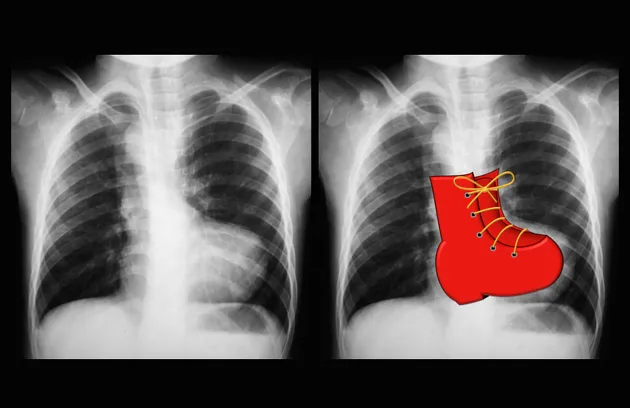

- Chest X-Ray (CXR) Clues:

- ToF: "Boot-shaped" heart; ↓ pulmonary vascular markings.